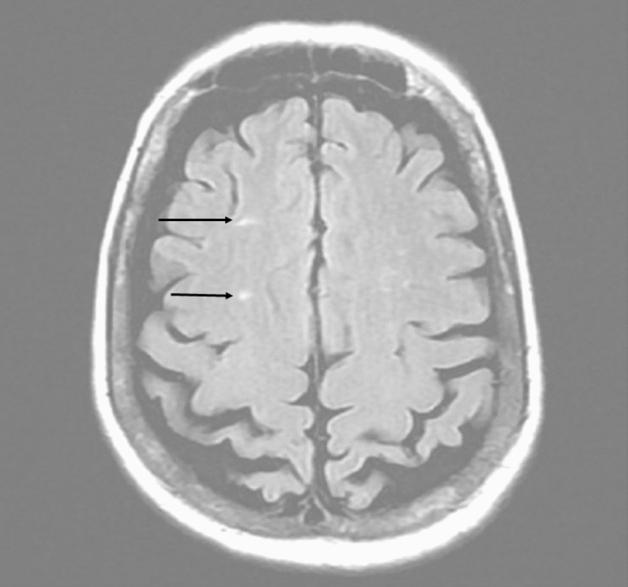

Sickle cell disease (SCD) is an inherited monogenic hemoglobinopathy characterized by formation of sickle erythrocytes under conditions of deoxygenation. Sickle erythrocytes can lead to thrombus formation and vaso-occlusive episodes that may result in hemolytic anemia, pain crisis and multiple organ damage. Moreover, SCD is characterized by endothelial damage, increased inflammatory response, platelet activation and aggravation, and activation of both the intrinsic and the extrinsic coagulation pathways. Cerebrovascular events constitute an important clinical complication of SCD. Children with SCD have a 300-fold higher risk of acute stroke and by the age of 45 about 25% of patients have suffered an overt stoke. Management and prevention of stroke in patients with SCD is not well defined. Moreover, the presence of patent foramen ovale (PFO) increases the risk of the occurrence of an embolic cerebrovascular event. The role of PFO closure and antiplatelet or anticoagulation therapy has not been well investigated. Moreover, during COVID-19 pandemic and taking into account the increased rates of thrombotic events and the difficulties in blood transfusion, management of SCD patients is even more challenging and difficult, since data are scarce regarding stroke occurrence and management in this specific population in the COVID-19 era. This review focuses on pathophysiology of stroke in patients with SCD and possible treatment strategies in the presence of PFO.

镰状细胞病(SCD)是一种遗传性单基因血红蛋白病,其特征是在缺氧条件下形成镰状红细胞。镰状红细胞可导致血栓形成和血管阻塞发作,从而导致溶血性贫血、疼痛危象和多器官损伤。此外,SCD 的特征还包括内皮损伤、炎症反应增加、血小板激活和加重,以及内源性和外源性凝血途径的激活。脑血管事件是 SCD 的一个重要临床并发症。患有 SCD 的儿童发生急性中风的风险高 300 倍,到 45 岁时,约有 25%的患者发生过明显中风。SCD 患者中风的管理和预防尚未得到很好的定义。此外,卵圆孔未闭(PFO)的存在会增加发生栓塞性脑血管事件的风险。PFO 闭合和抗血小板或抗凝治疗的作用尚未得到很好的研究。此外,在 COVID-19 大流行期间,考虑到血栓形成事件的发生率增加以及输血困难,SCD 患者的管理更加具有挑战性和困难,因为在 COVID-19 时代,针对该特定人群中风发生和管理的数据很少。本文重点介绍 SCD 患者中风的病理生理学以及 PFO 存在时的可能治疗策略。